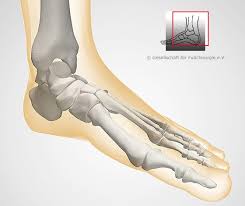

Fußknochen an der seite. Nachdem der erste Anlauf ein Eltern- Lehrerinnen- Team auf die Beine zu stellen im vergangenen Jahr an körperlichen Gebrechen gebrochener Fußknochen gescheitert war starteten wir in diesem Jahr einen neuen Versuch lauffreudige Menschen für den Hanauer Stadtlauf zu begeistern. Der Fuß besteht aus Fußwurzelknochen Mittelfuß und den fünf Zehen auch Vorfuß genannt. Der Fuss ist an der Stelle mit dem Körper verbunden wo Knochen des Rückfusses auf das Schien- und Wadenbein treffen Knöchel.

Andere Erkrankungen der Füße entstehen durch Krankheiten die viele Bereiche des Körpers betreffen wie Diabetes mellitus Gicht oder andere Arthritisformen. Die Knochen des Fußskeletts werden durch zahlreiche Bänder zusammengehalten und sind durch Gelenke miteinander verbunden. Alle von diesen Cookies erfassten Informationen werden aggregiert und sind deshalb anonym.

Den gesamten Komplex bilden außerdem Gelenke Fußwurzelgelenke Gelenke der Mittelfußknochen und Zehengelenke viele für die. Eine weitere Ursache für Schmerzen an der Fußaußenseite ist die Fraktur des fünften Mittelfußknochens. Der menschliche Fuß besteht aus 26 Knochen.